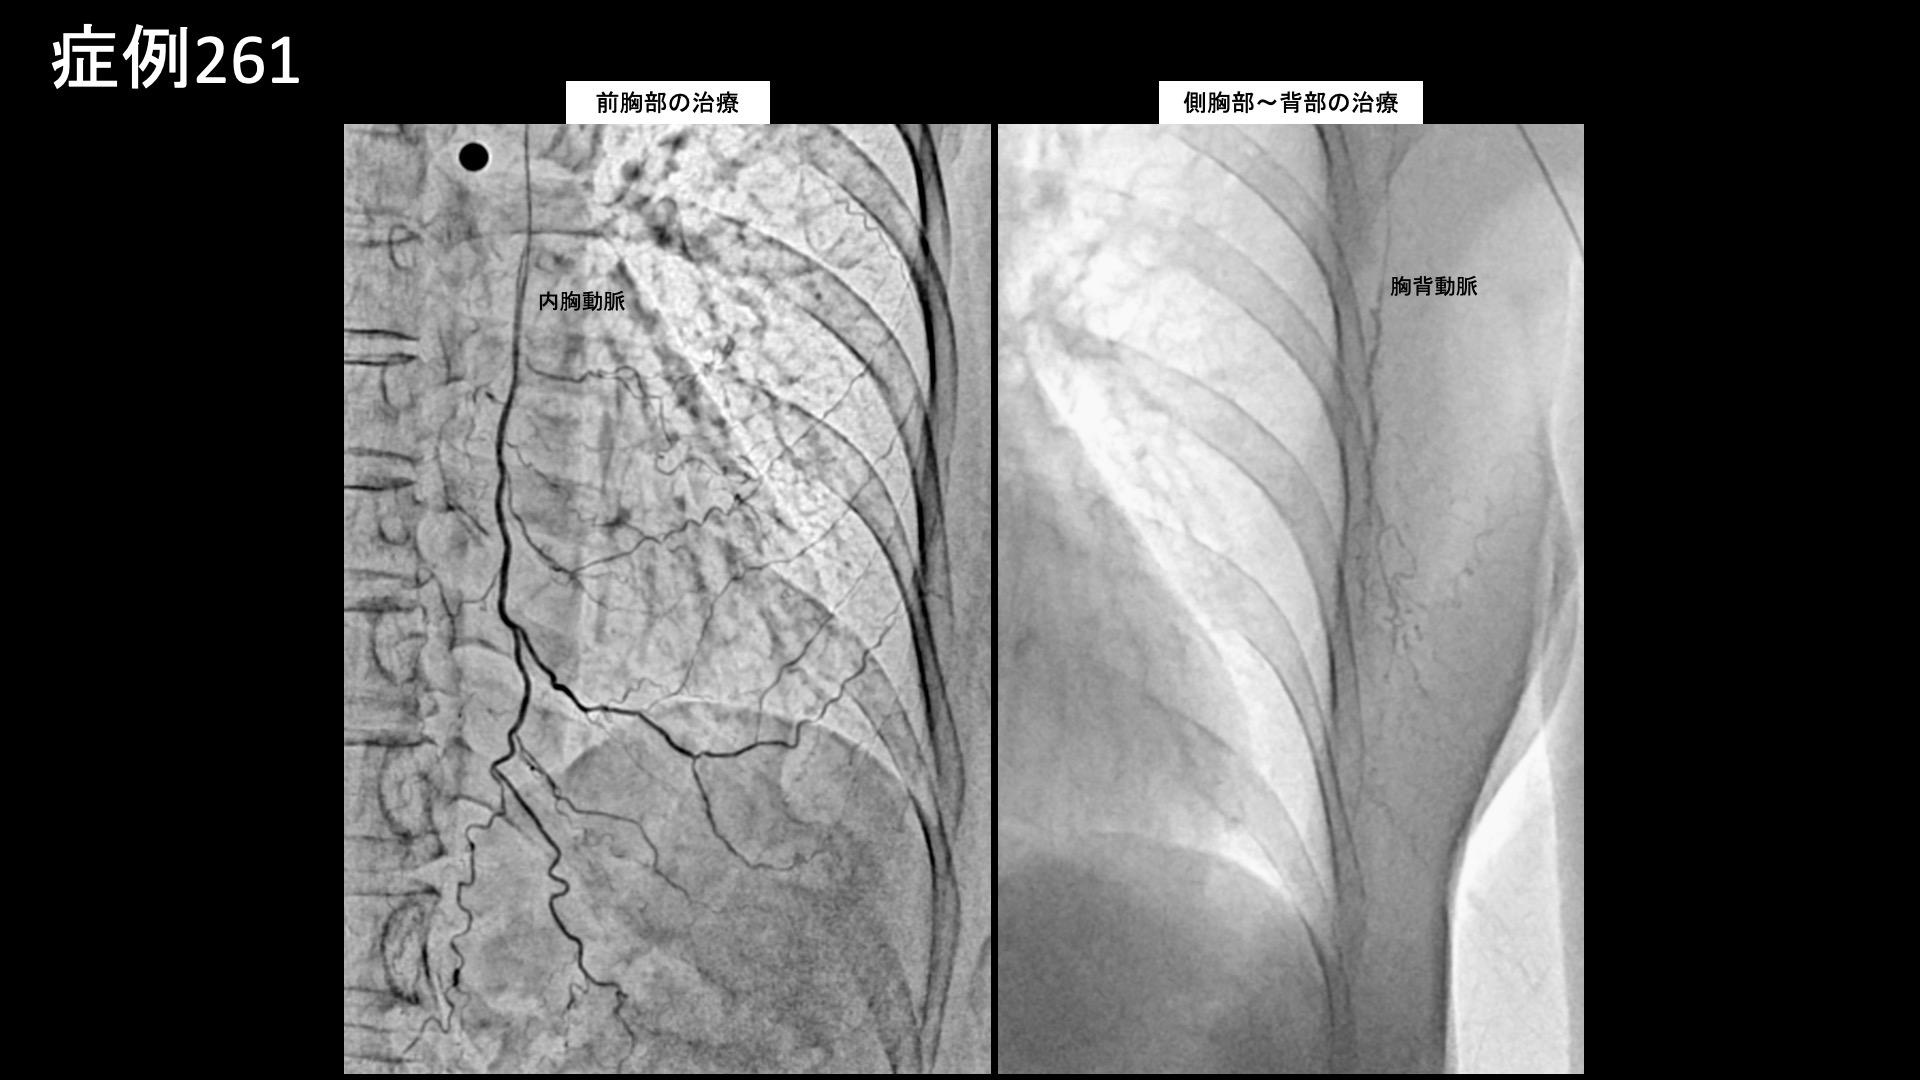

帯状疱疹後神経痛はモヤモヤ血管が描出されやすい疾患ではありませんので、通常、モヤモヤ血管を描出するためのDSA撮像という特殊な撮影条件で撮影することはありません。解剖学的な知識、および再現痛をたよりに治療を進めていきます。写真では、前胸部の主要責任血管である内胸動脈、脇から背中にかけて重要になってくる胸背動脈、および肋間動脈の血管造影画像を示しています。それぞれ再現痛が認められました。治療のやり残しがないよう、必要十分な範囲を治療して終了しました。

*再現痛とは、薬液投与時に普段の痛みが一定程度再現される現象です。責任血管の同定のための参考とします。